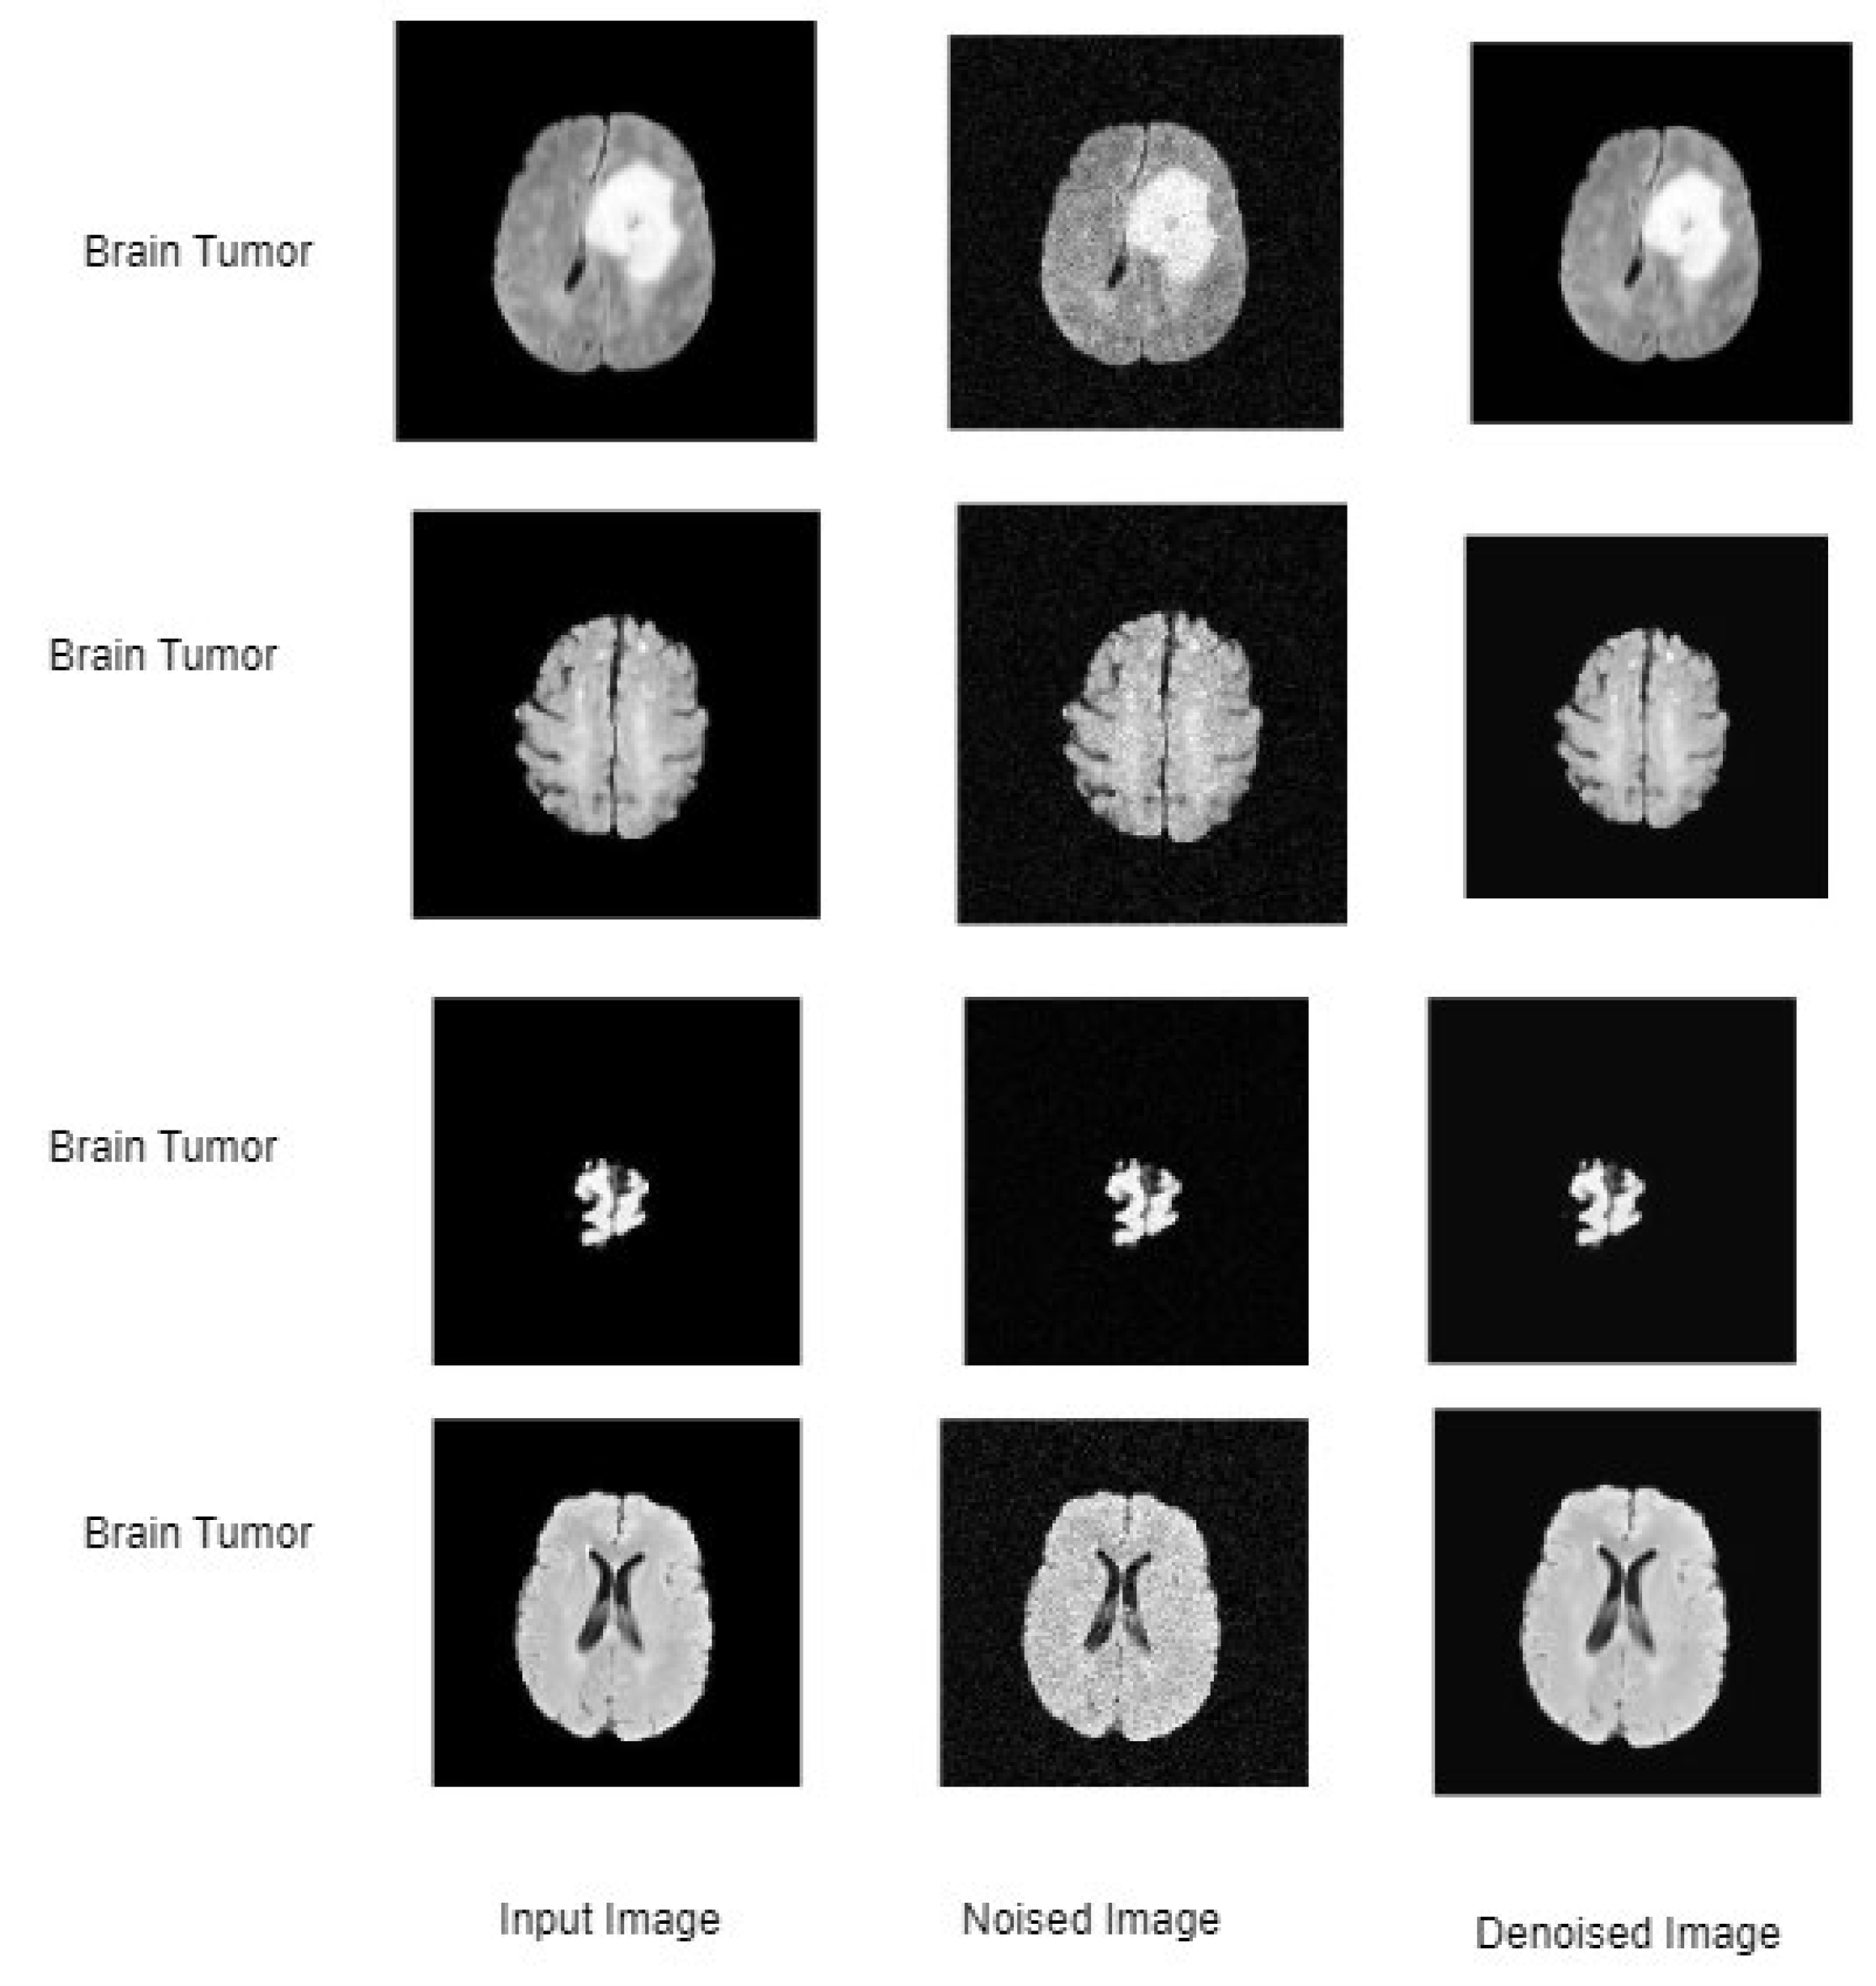

Figure 2 shows the sample input and noised and denoised brain MRI images. Noising and denoising are standard techniques used in MRI imaging to improve image quality. Denoising helps reduce the impact of artifacts caused by noise in the acquisition process. MRI imaging involves taking a series of X-ray images from different angles around the body, which are then reconstructed into a 3D image using complex algorithms. However, many factors, such as tissue thickness and density, can affect X-ray photons passing through the body, causing image noise and artifacts.

Denoised images of brain MRI images.

Adding artificial noise to MRI images can help simulate the impact of noise on image quality and can support test image processing algorithms. On the other hand, denoising techniques can be applied to remove unwanted noise and improve image clarity. There are various methods for noising and denoising in MRI imaging, including statistical methods. Examples include filtering, wavelet techniques, and CNN models. The choice of method depends on the specific requirements of the application and the equipment included.